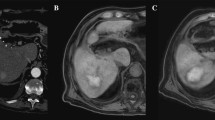

Images in a 50-year-old man with well-differentiated hepatocellular carcinoma. At preablation MR imaging, the axial unenhanced T1-weighted image (A) shows hyperintense tumor (white arrow), and axial (B) and coronal (C) hepatobiliary phase images demonstrate hypointense tumor (white arrows). Tumor size is 26 mm, and TLCR on axial unenhanced T1-weighted and HBP imaging are 0.19 and 2.04. After radiofrequency ablation for tumor, axial unenhanced T1-weighted imaging (D) does not distinguish from a broad hyperintense ablation margin from the central hyperintense tumor (black arrow). The ablation margin is classified as indefinite. Axial (E) and coronal (F) hepatobiliary phase images show central hyperintense tumor surrounded by a broad intermediate-intense ablation margin (black arrows). The ablation margin is classified as visible. Using combined images, the status of the ablation margin is AM zero. During 8 months follow-up, there is no evidence of local tumor progression

Images in a 80-year-old man with moderately differentiated hepatocellular carcinoma. At preablation MR imaging, the axial unenhanced T1-weighted image (A) shows an hypointense tumor (white arrow), and axial (B) and coronal (C) hepatobiliary phase images show a hypointense tumor (white arrows). Tumor size is 23 mm, and TLCR on axial unenhanced T1-weighted and HBP imaging are 0.65 and 1.94. After radiofrequency ablation for the tumor, axial unenhanced T1-weighted imaging (D) shows a collapsed central hypointense tumor and a broad hyperintense ablation margin (black arrow). This ablation margin is classified as visible. Axial (E) and coronal (F) hepatobiliary phase images show a central hypointense tumor with an intermediate-intensity ablation margin (black arrows). This ablation margin is classified as visible. Using combined images, the status of the ablation margin is AM plus. During 34 months follow-up, there is no evidence of local tumor progression